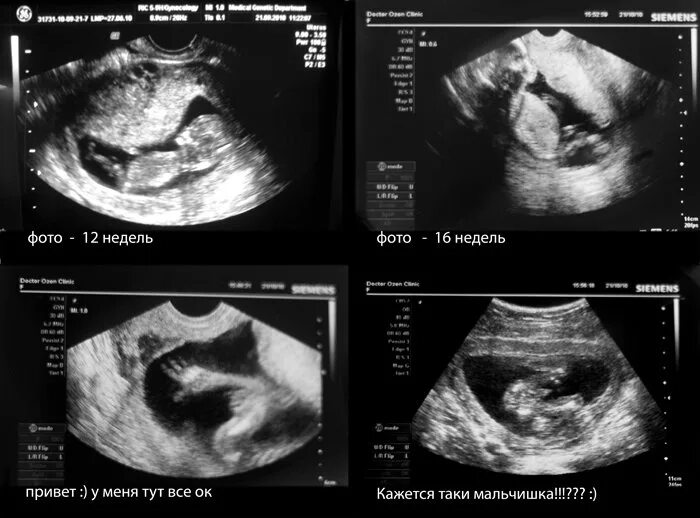

На каком узи можно узнать пол ребенка